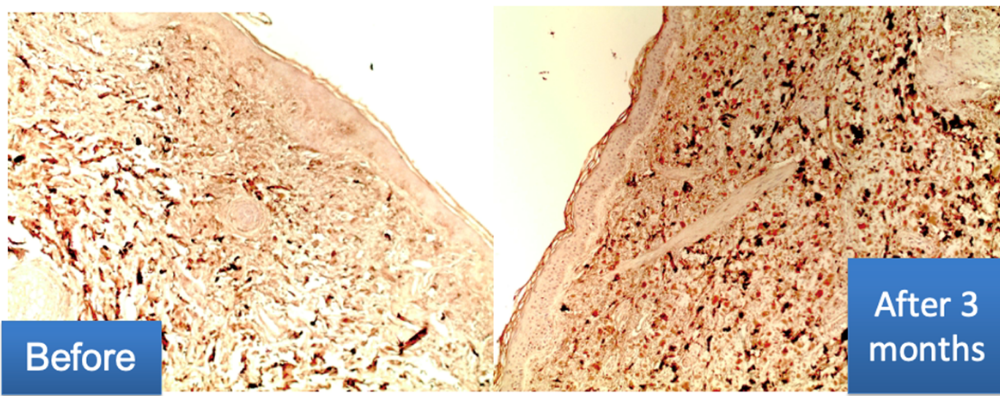

Imūnhistoķīmiskā izmeklēšana:

- Kolagēna III saturs dermā ir ievērojami palielināts.

- Gareniski orientētu šķiedru veidošanās